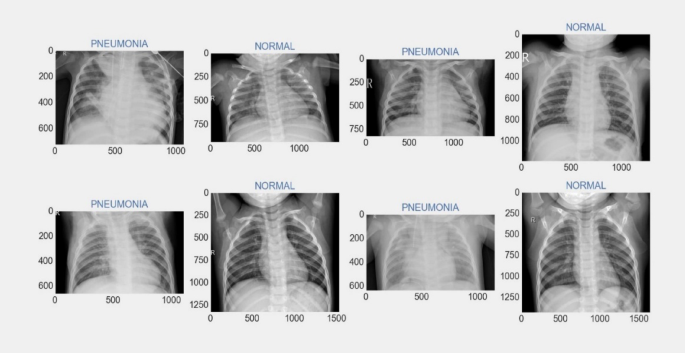

The computer that was used for this study has a 2.10 GHz power of CPU, 16 GB of RAM, and is associated with the i7 12th gen Intel processor. The simulation was carried out using Python 3.10.9, with libraries Tensorflow, Keras, Pandas, Numpy, and Matplotlib used for preprocessing, implementing the suggested transfer learning method, and for performance evaluation. Figure 2 represents some sample Chest X-ray images for normal and pneumonia patient. All the vision models that we leveraged in our analysis; we compared their performance using the widely-used confusion matrix (CM) as depicted in Fig. 3. We have shown the CM for Xception, VGG16, and ResNet152V2 in Fig. 3a–c respectively. It is evident from CM that ResNet152V2 produced a higher number of correct predictions.

Some Sample chest X-ray images for normal and pneumonia patient.